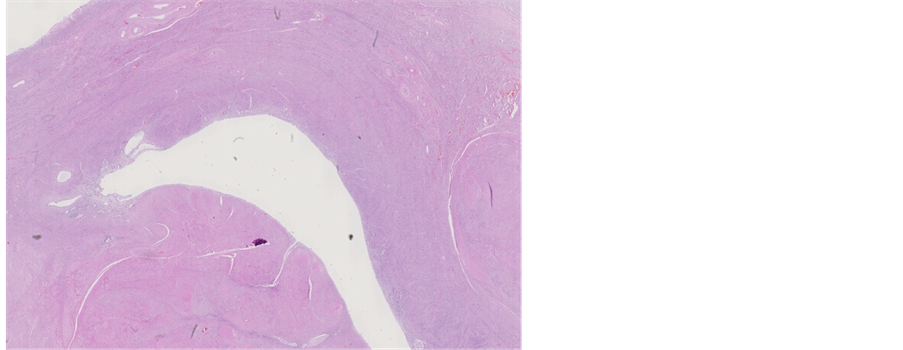

13 months later the patient died. The pathologist performed an autopsy in attendance of the treating psychiatrist. At autopsy extensive areas of necrotizing inflammation and abscess were found in liver (Figure 11). Sepsis and bacteraemia were confirmed. In addition there were multiple inflammatory areas around the pancreas. A focus of myocardial infarction (weeks or months old) was detected with extensive athero- sclerosis of coronary arteries. No carcinoma could be found in uterine corpus or cervix (Figures 12-14). Only presence of adenomyosis and leiomyoma was described in uterine corpus. Myocardial infarction, aggravated by poor functional status of organism due to sepsis, was concluded to be a cause of death.

Figure 14. Microscopic appearance of the endometrial and myometrial tissue from post-mortem examination-uterine leiomyoma is seen, H&E staining, ×1.25.